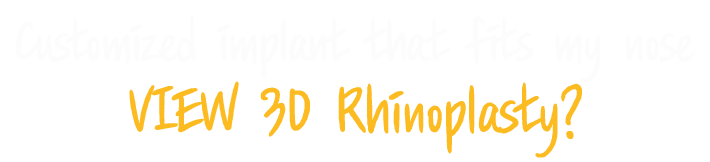

This is 1:1 customized rhinoplasty that allows you to create the most suitable implant for your nose by using 3D printer to create the patient’s skeleton, cartilage, skin tissue, and muscle with data obtained from 3D-ct images.

Because it is possible to manufacture a customized implant that fits perfectly to the nasal bone, it is safe and there is little worry about reoperation as it significantly reduces side effects such as bending, silicone seepage, and lifting.